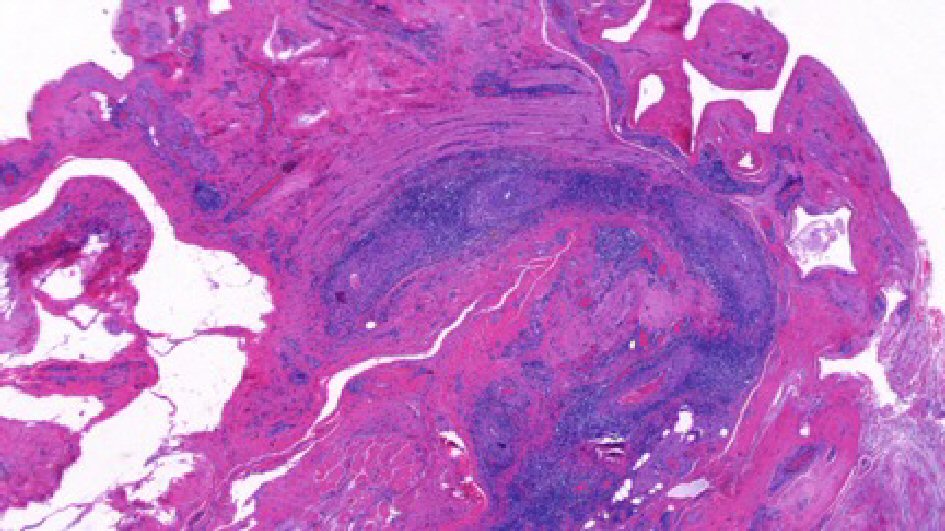

On admission he was continued on the same dose of oral prednisone until biopsy results were obtained for definitive diagnosis. His abdominal pain and hematuria had completely resolved, and testicular pain was improving each day. Given the testicular symptoms, the patient underwent bilateral testicular and paratesticular tissue biopsy to rule out systemic vasculitis. The bilateral paratesticular biopsies demonstrated focally necrotizing vasculitis affecting small and medium vessels with fibrinoid necrosis (Fig. 1, 2). Staining for IgG and IgG4 revealed rare scattered IgG4 positive plasma cells among a population of IgG positive cells. Immunofluorescence was otherwise negative for an immune complex mediated vasculitis as the complement and fibrinogen staining related to focal, active areas of inflammation involved by fibrinoid necrosis. Testicular tissue was negative for inflammation, infarction, or parenchymal vasculitis.

![]() Click for large image | Figure 1. Left paratesticular tissue with perivascular infiltrates containing of lymphocytes and plasma cells (H&E, 20 × original magnification). |

While our patient’s symptoms were highly suggestive of vasculitic etiology, histopathologic finding is the most definitive diagnosis of PAN. Active lesions of the affected arteries in the PAN typically demonstrate areas of fibrinoid necrosis and neutrophilic infiltration, as seen in the biopsy slide of our patient [2]. This differs from granulomatosis with polyangiitis, formerly known as Wegener granulomatosis, which demonstrates necrotizing granulomatous inflammation of small and medium-size vessels in addition to PR3-ANCA positivity. Another consideration in the differential of testicular pain among systemic vasculitis is Henoch-Schonlein purpura (HSP). However, HSP is associated with the presence of immune complexes containing IgA along with its cutaneous manifestation of palpable purpura. Given the high index of suspicion for vasculitis in the absence of palpable testicular mass, orchiectomy was avoided as testicular biopsy was sufficient to establish the diagnosis.